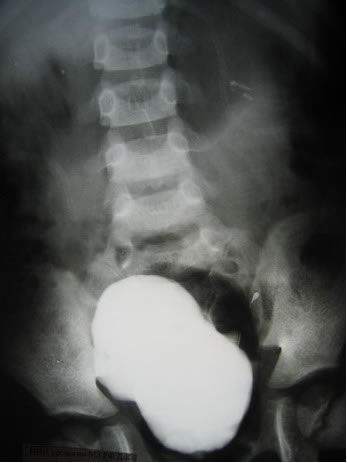

Антеградная уретерография справа

Антеградная уретерография слева